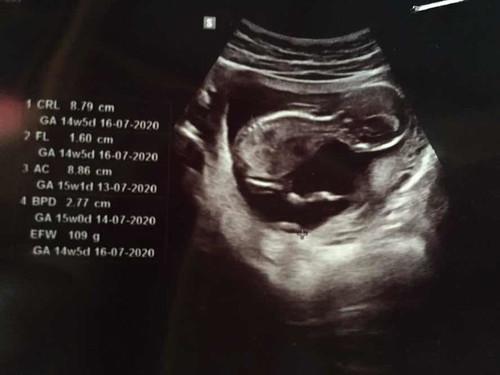

15w+5แล้วค่ะ แม่ๆรู้เพศน้องสัปดาห์ที่เท่าไหร่กันค่ะ

บ้านนี้ตรวจนิฟตี้ค่ะ รู้ตั้งแต่ไตรมาสแรกเลย ถ้าด้วยวิธีซาวด์ จะฟันธงได้ตอน 20 วีคขึ้นไปค่ะ อวัยวะโตพอแล้ว